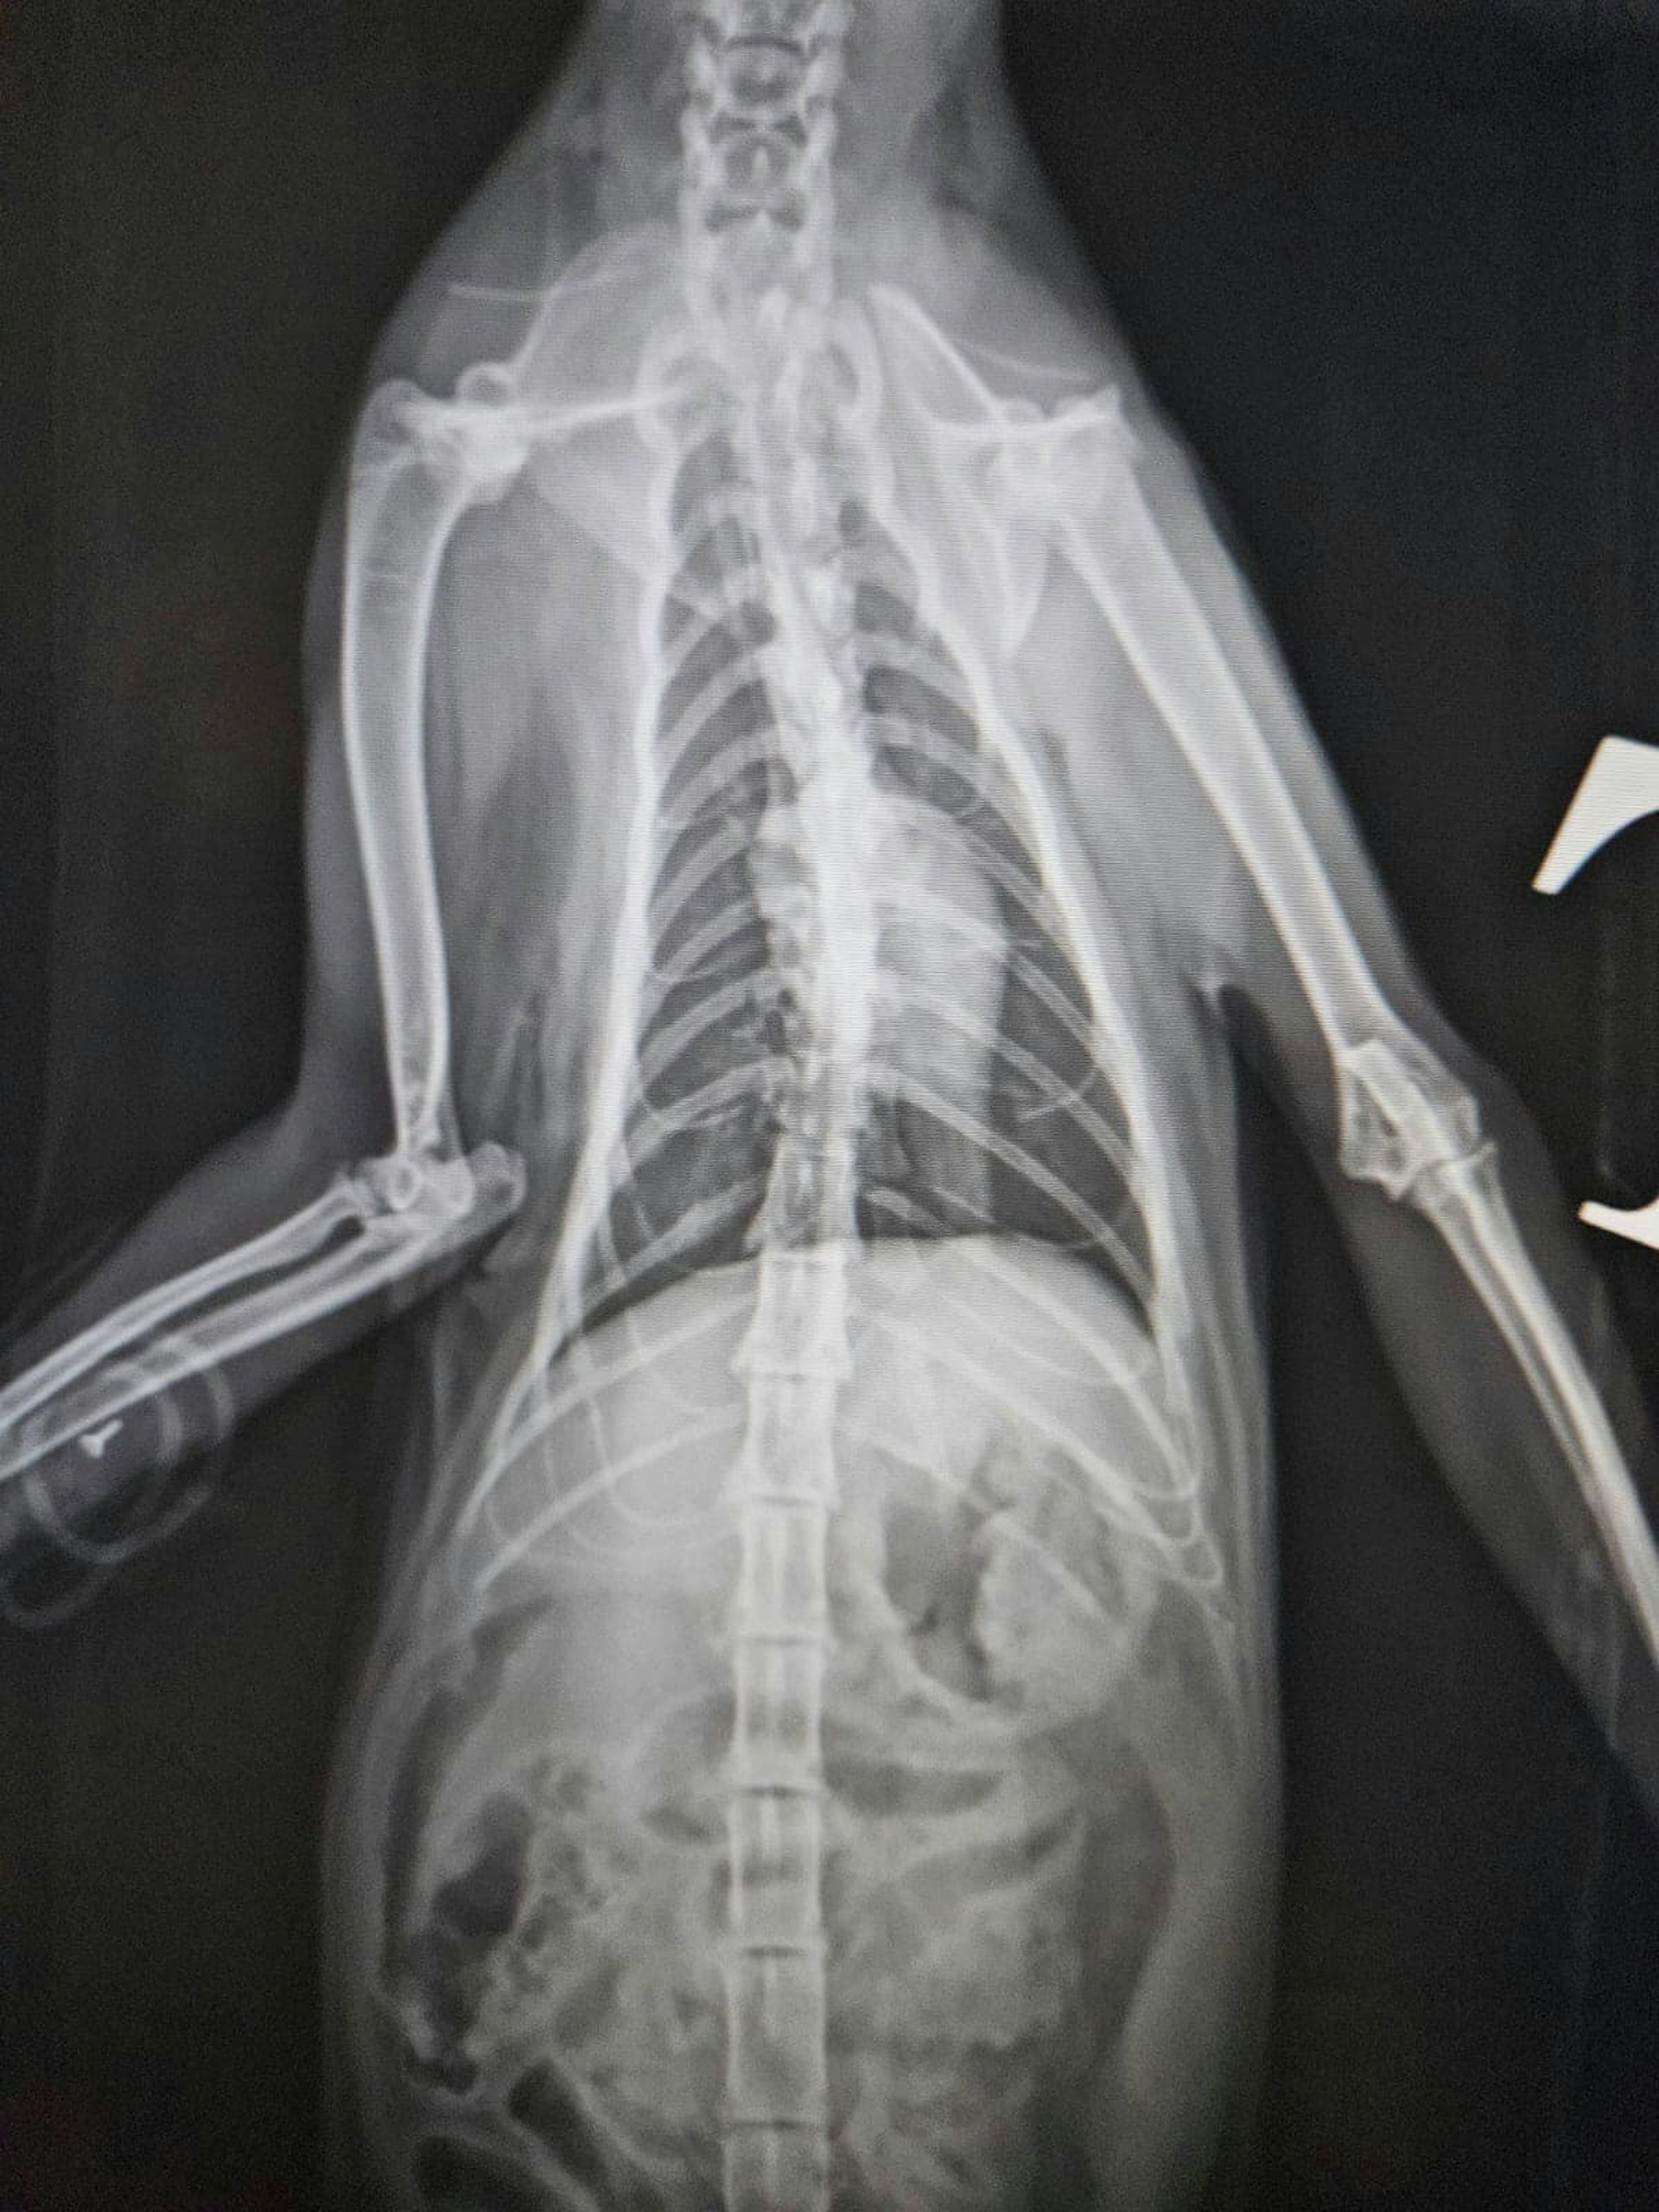

受傷貓隻接受X光檢查。(facebook專頁「毛守救援」圖片)